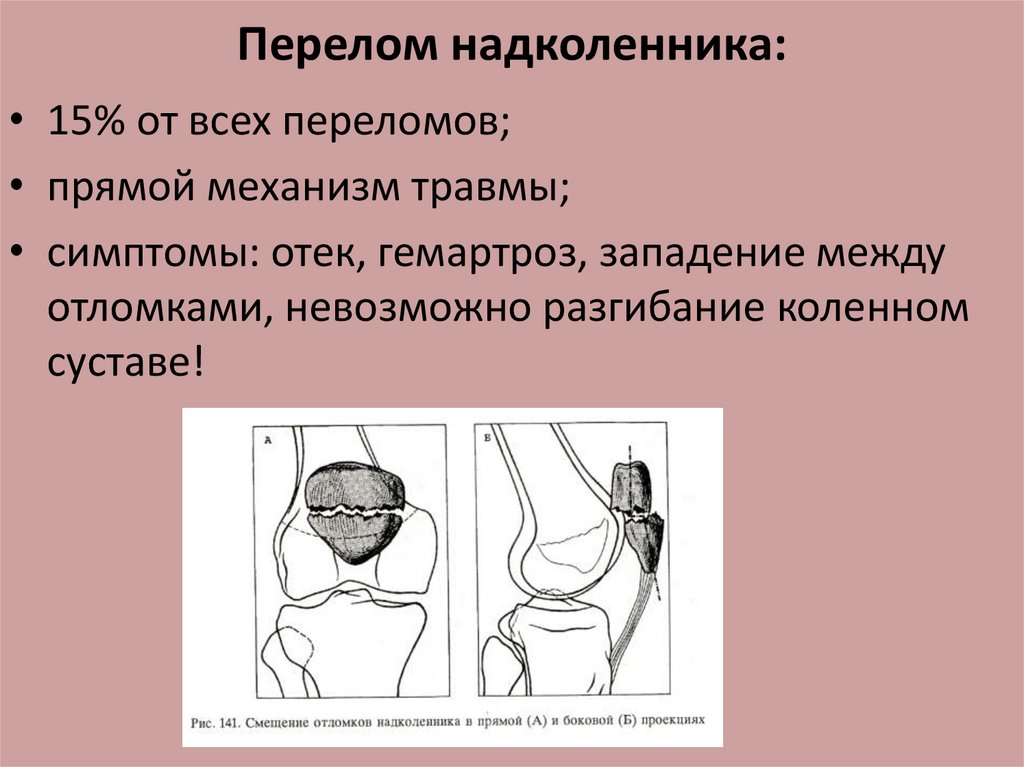

Варианты перелома надколенникаЧаще всего встречаются горизонтальные переломы. Так как к верхней части надколенника крепится сухожилие четырехглавой мышцы, которая тянет надколенник вверх, то, как правило, костные отломки разобщаются и между ними появляется щель. Такой перелом уже называется переломом со смещением.

Отек. Переломы надколенника – внутрисуставные, т.е. линия перелома «проходит по скользящим суставным поверхностям. Как и при любом переломе пвозникает кровотечение, и, поскольку линия перелома сообщается с полостью сустава, сам сустав вскоре наполняется кровью, отекает. Такое состояние называют гемартрозом, что в переводе с латыни означает «кровь в суставе». Гемартроз может привести к чувству распирания, а движения за счет этого могут быть резко ограниченными.

Невозможность разогнуть ногу или поднять выпрямленную ногу. Этот признак бывает не всегда, что зависит от варианта перелома.

Деформация. При переломах надколенника иногда можно увидеть или прощупать западение в области надколенника.

Классический симптом, который присутствует при горизонтальных переломах надколенника (самый распространенный вариант перелома) – невозможность разогнуть или поднять выпрямленную ногу.

Нарушения функции конечности при переломах наколенника зависят от характера перелома и степени повреждения его мышц. При переломах надколенника без смещения или с расхождением отломков меньше, чем на полсантиметра связочный аппарат обычно не повреждается. Большее расхождение отломков надколенника всегда указывает на разрывы поддерживающих (боковых) связок, поэтому при сокращении четырехглавой мышцы бедра фрагменты надколенника смещаются на несколько сантиметров. При переломах надколенника в коленном суставе всегда появляется кровь (гемартроз). Объем коленного сустава увеличивается, активные движения в нем становятся невозможными, конечность находится в выпрямленном положении, поднять ее больной не может. Отломки надколенника легко прощупываются.

При переломах надколенника в коленном суставе всегда появляется кровь (гемартроз). Объем коленного сустава увеличивается, активные движения в нем становятся невозможными, конечность находится в выпрямленном положении, поднять ее больной не может. Отломки надколенника легко прощупываются.